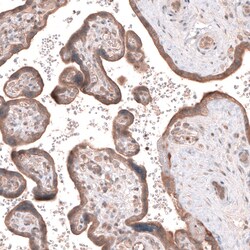

Invitrogen™ ACSL3 Polyclonal Antibody

Brand: Invitrogen™ PA582427

| Immunohistochemistry (Paraffin), Western Blot | |